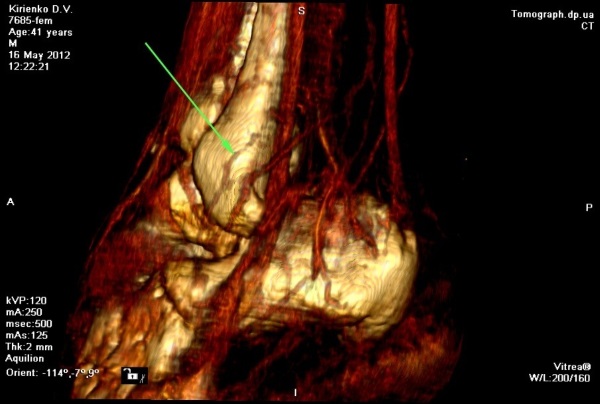

Послеоперационный период протекал гладко, без каких либо осложнений. Оба лоскута прижили в реципиентных зонах, обеспечив тем самым восстановление кожного покрова, утраченного объема мягких тканей, покровной, каркасной, кинематической и эстетической функций (Рис 3). Кроме того, наличие постоянного артериального кровоснабжения этих лоскутов обеспечило устойчивое улучшение кровообращения или реваскуляризацию скальпированных и поврежденных костных структур стопы за счет включения в состав лоскутов двух артерий: суральной и кожной перфорантной ветви от малоберцовой артерии. Последние хорошо визуализируются на КТ- ангиографическом исследовании с 3-D моделированием (Рис 4).

Рис. 4. Вид распределения сосудистой сети левой стопы после операции на КТ- ангиографическом исследовании с 3-D моделированием; Слева – со стороны медиальной поверхности, где рана закрыты «суральным» лоскутом с дистальным основанием определяется a. suralis (стрелка) в проекции питающей ножки лоскута; Справа – со стороны тыльно-латеральной поверхности, где рана закрыта латеральным надлодыжечным лоскутом определяется перфорантная ветвь – ramus cutaneous от a. fibularis (стрелка) в проекции питающей ножки лоскута.